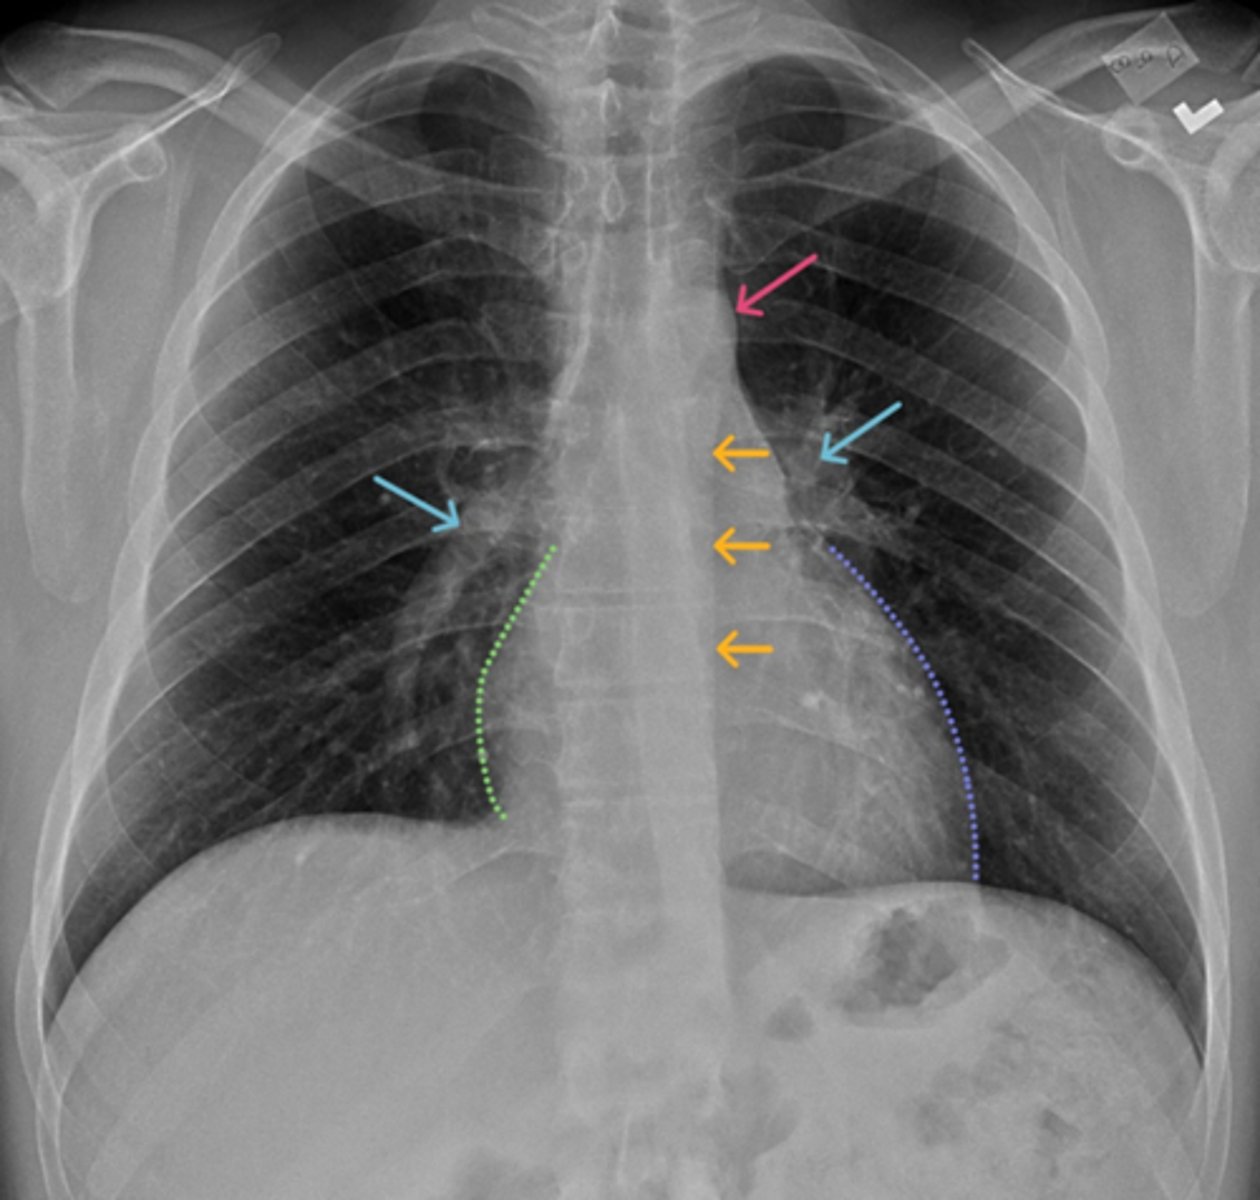

Aortic knob/arch

Pink Arrow

Left ventricle and border of the heart

Purple Line

Pulmonary arteries

Blue Arrows

Normal film

Interpretation